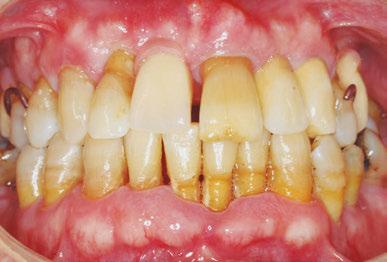

–Implantes híbridos en pacientes con antecedentes de periodontitis, por el Dr. Antonio Arnau y cols. [90]

—¿Son preocupantes los índices de periimplantitis actualmente? ¿Y las intervenciones de implantoplastia? —Los índices de periimplantitis son muy elevados, ya que las enfermedades periodontales se cifran en valores superiores al 20% de los implantes dentales colocados a lo largo de los años. Estas son cifras muy elevadas y hemos de poner solución. El problema es muy serio, ya que es evidente que una falta de higiene favorece estas enfermedades, pero también es responsable la genética, el diseño de los implantes dentales, las cargas mecánicas… El problema tiene muchas caras y no es fácil de abordar. La implantoplastia evita la extracción del implante dental, pero se mecaniza en boca y eso causa graves problemas; uno de los más peligrosos son las partículas de metal que se desprenden en los tejidos. Hemos podido comprobar la citotoxicidad de estas partículas, provocando procesos inflamatorios. Asimismo, hay partículas de tamaño tan pequeño que no son reconocidas por los macrófagos y las consecuencias son todavía desconocidas. Hemos de conocer que estas partículas se desprenden por fractura de la superficie y son tan energéticas que se oxidan con gran rapidez, pudiendo causar procesos de metalosis. Aparte de los efectos de reacción a cuerpo extraño de las partículas, hay una pérdida de propiedades mecánicas del implante dental y las tensiones internas causadas por la mecanización facilitan la corrosión y liberación de iones. Estos resultados han comenzado a ser publicados por investigadores de la red nacional en diferentes publicaciones de revistas de alto impacto. Los investigadores españoles son reconocidos por los trabajos en la caracterización y consecuencias de la implantoplastia y estamos siendo punteros en esta investigación, así como en sistemas bactericidas y bacteriostáticos muy prometedores.